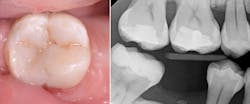

In this specific clinical case, it is evident that the consideration of pursuing indirect restorations arises from the outset. With existing amalgam restorations, coupled with cracks and caries (figure 1), this molar necessitates optimal fatigue resistance, particularly as the adjacent molar is absent. Our primary objective, irrespective of the materials under consideration, is to preserve the greatest amount of healthy tooth structure during the procedure to ensure longevity. Additionally, this molar may serve as a potential anchor for orthodontic uprighting, should the patient opt for implant placement adjacent to the tooth.

The incorporation of caries-indicating dye proves highly beneficial in clinical scenarios such as this one.4 As mentioned earlier, the primary consideration in selecting a replacement material is the comprehensive removal of all elements requiring extraction, including existing restorations, caries, and decalcification. Once this removal process is completed, and we are left with a foundation of healthy and restorable tooth structure, it becomes apparent that the number and depth of the remaining walls can give rise to concerns about shrinkage and the C-factor (figure 2). Additionally, if we opt for indirect restorations, it is essential to continue the preparation with an awareness of factors such as material thickness, undercuts, and the path of insertion.5